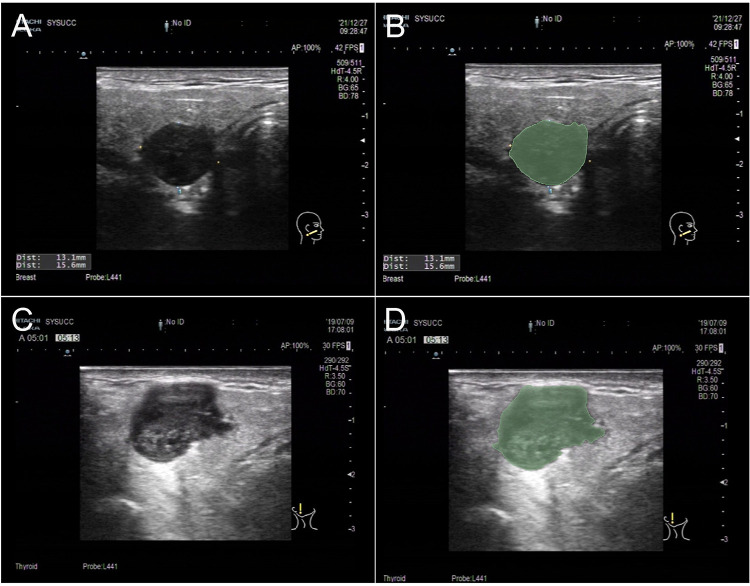

Methods: Grayscale ultrasound (US) images of parotid gland nodules were segmented, and radiomics features were extracted. An support vector machine (SVM) model was built using the Least Absolute Shrinkage and Selection Operator (LASSO) algorithm for feature selection. Different SVM models were built based on clinical characteristics, radiomics features, and a combination of these features. Performance of the models was assessed using the area under the curve (AUCs), sensitivity and specificity.

Abstract Image